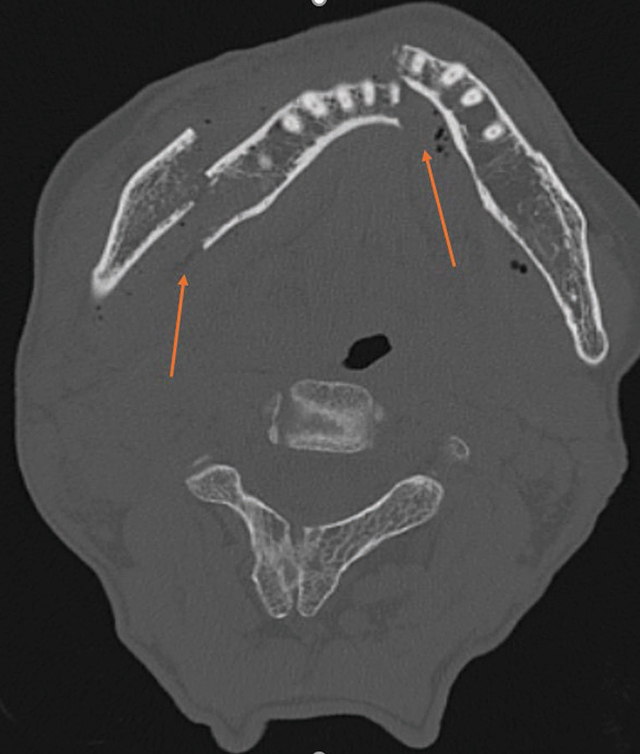

Carotid-cavernous fistulas (CCFs) are abnormal connections between the carotid arteries and the cavernous sinus, posing significant neuro-ophthalmologic risks. This report presents a rare case of bilateral post-traumatic CCFs, focusing on clinical presentation, diagnosis, and management. Symptoms mimic conjunctivitis, causing diplopia, exophthalmos, and ophthalmoplegia. Diagnosis relied on computed tomography, magnetic resonance angiography, and digital subtraction angiography. Management involved transarterial embolization with coils, achieving successful outcomes. This highlights the importance of timely intervention and comprehensive imaging to prevent complications. Teaching point: This case report details a rare instance of bilateral post-traumatic carotid-cavernous fistulas, emphasizing clinical presentation, diagnostic evaluation, and management.

颈动脉海绵窦瘘(CCFs)是颈动脉和海绵窦之间的异常连接,对神经眼科构成重大风险。本报告介绍了一例罕见的双侧外伤后 CCF 病例,重点阐述了临床表现、诊断和处理方法。症状类似结膜炎,导致复视、眼球外翻和眼肌麻痹。诊断主要依靠计算机断层扫描、磁共振血管造影和数字减影血管造影。治疗包括使用线圈进行经动脉栓塞,取得了成功。这凸显了及时干预和全面成像对预防并发症的重要性。教学要点:本病例报告详细介绍了一个罕见的双侧创伤后颈动脉海绵瘘病例,强调了临床表现、诊断评估和处理方法。